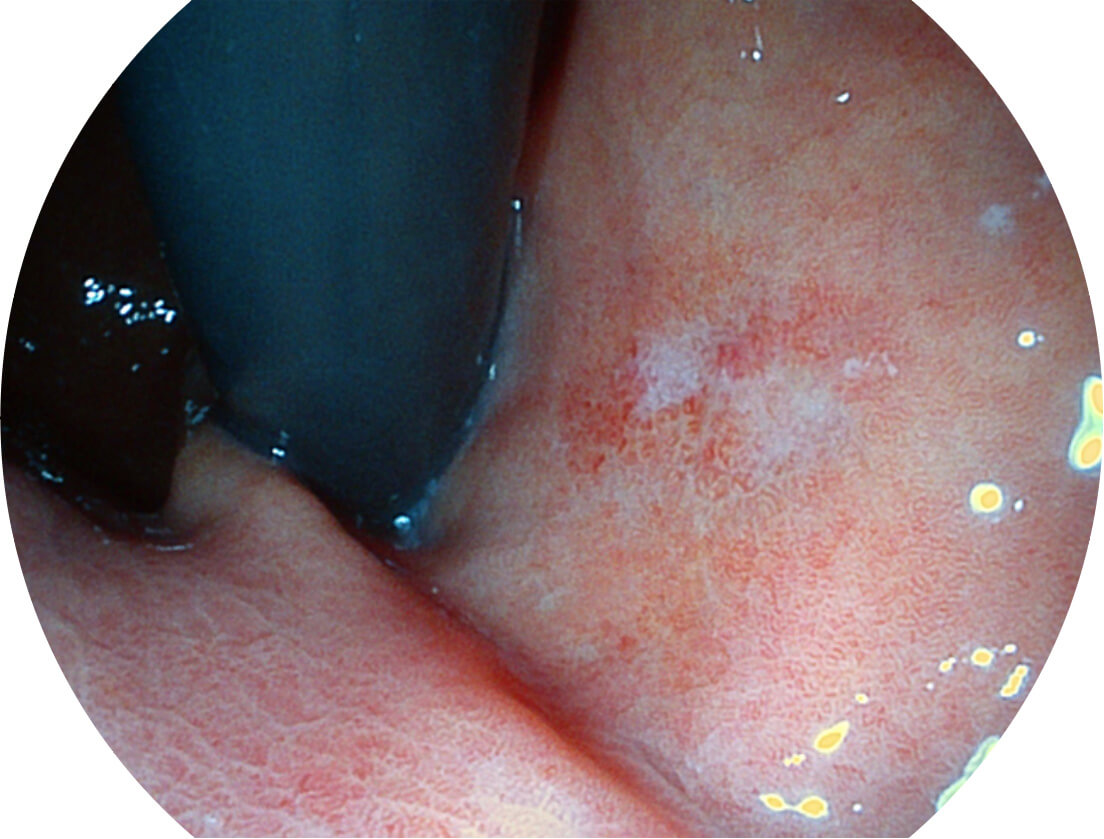

白光图像

SFI图像

Spectral Focused lmaging, SFI

图像具有高亮度、高黏膜血管颜色对比度的特点,且不改变粘液、食物残渣、粪便的基本颜色,可在中远景下进行观察,助力消化道早期疾病的诊断。